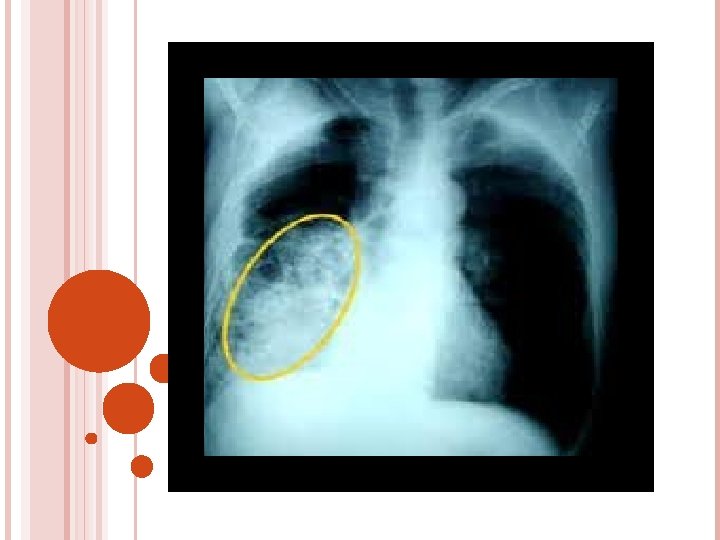

KLEBSIELLA Greater in elder / alcoholics Mortality – 40 – 50% Tissue necrosis , bronchopneumonia , lung abscess , lobar consolidation Cephalosporin , amino glycosides , , Antipseudomonal penicillin , monobactum , quinolones

DIAGNOSTIC STUDIES History collection , physical examination Chest X-Ray lab Microbiology serology ABG